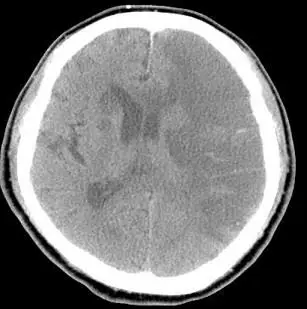

這張非顯影劑頭部 CT(水平切面)可見:

1. 左側額-顳-頂葉大片低密度區,灰白質分界消失,符合急性缺血性腦梗塞。

2. 皮質迴及腦溝受壓,顯示腦實質腫脹。

3. 左側側腦室受擠壓、正中縱裂向右偏移,證實顱內壓上升及中線移位。 整體呈現惡性左側 MCA 梗塞之細胞毒性水腫,需要積極降腦壓。